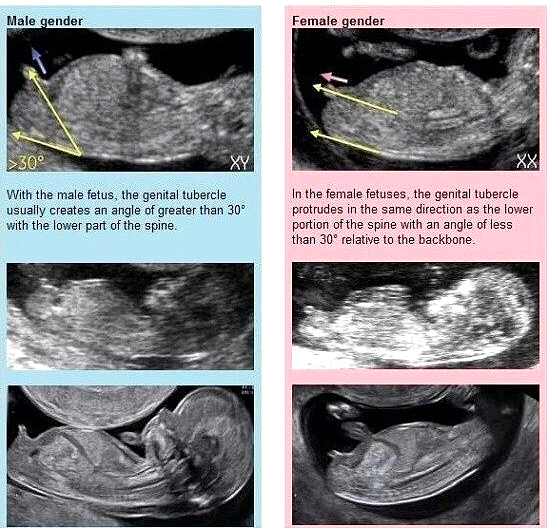

4. 12주 초음파 각도 법

일반적으로 많은 분들이 사용하는 성별 추측 방법 중 하나이다. 각도 법은 임신 11~13주 차에서 태아가 편안하게 누워 있을 때 확인이 가능하다. 생식기와 척추가 30도 이상 경사가 지면 아들, 평행이거나 30도 아래일 경우 딸일 확률이 높다고 한다.

12주 차에는 아들, 딸 상관없이 성기가 튀어나와 육안으로 성별을 구분하기가 어려우며 14주 차가 되면서 여성의 성기가 점차 들어가 16주 차가 되는 날 성별을 육안으로 구분하기 쉽다. 물론 성기를 확인하는 동안 탯줄의 위치에 따라 정확히 확인이 불가능한 경우도 있지만 최근 초음파 기술이 좋아져서 큰 이상이 없는 경우 확인이 가능하다.

각도 법 설명